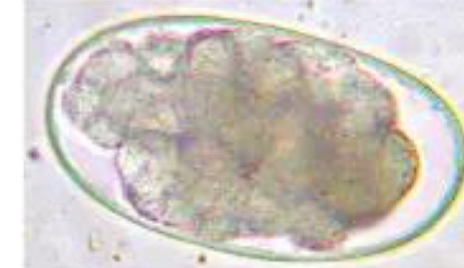

Toxascaris leonina. (Canine and Feline Roundworm)

Dx: Fecal float

Other info:

Smooth outer shell

Ground glass centre